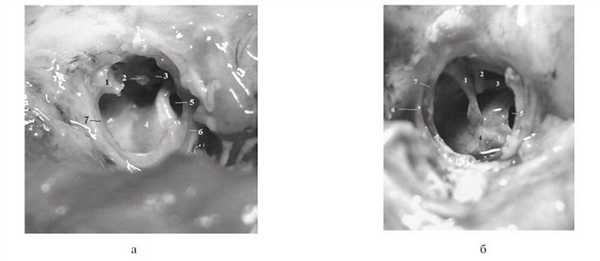

Мыс у новорожденных до 30 нед гестации полностью занимает нижнюю часть барабанной полости, гипотимпанум отсутствует (рис. 2, а на цв. вклейке). Рисунок 2. Макропрепарат барабанной полости. Барабанная полость новорожденного на сроке гестации 23 (а) и 31 (б) нед (барабанная перепонка удалена). 1 — рукоятка молоточка (частично удалена — а), 2 — длинная ножка наковальни, 3 — стремечко, 4 — промонториум, 5 — окно улитки, 6 — барабанное кольцо, 7 — участок барабанной перепонки.

В верхних отделах барабанной полости располагаются слуховые косточки. Со временем промонториум по мере роста черепа отходит кзади, уплощается и уже в срок около 30 нед гестации появляется область гипотимпанума (рис. 2, б на цв. вклейке).